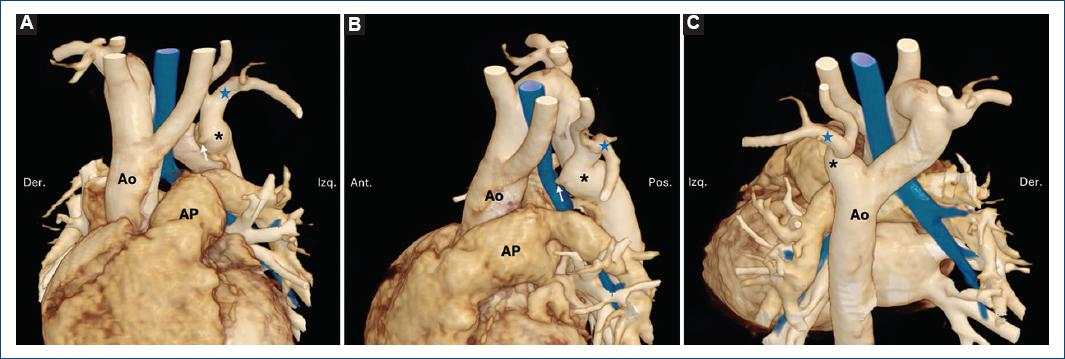

En cuanto al doble arco aórtico (Figs. 4 a 6), los subtipos fueron con dominancia derecha en el 4.5% y con dominancia izquierda en el 1.8%.

Figura 4 Doble arco aórtico. Reconstrucciones volumétricas a partir de tomografía cardiaca en vista anterior (A), posterior (B) y craneal (C). Paciente de 8 meses abordada por reflujo gastroesofágico y esofagograma que mostró estenosis en el esófago medio. Se demostró un doble arco aórtico. Se observa la imagen característica con los dos arcos y la emergencia simétrica de ambos vasos supraaórticos desde cada uno. En azul se representa la vía aérea; el esófago (no demostrado) es posterior a esta (asterisco), pero está también incluido dentro del anillo vascular. AoA: aorta ascendente; AoD: aorta descendente.

Figura 5 Doble arco aórtico con conducto arterioso persistente. Reconstrucciones volumétricas a partir de tomografía cardiaca en vista anterior (A), lateral izquierda (B) y craneal (C). Paciente de 1 mes con dextromorfismo y fisiología univentricular. Se demuestra doble arco aórtico: el arco dominante señalado con asterisco y el no dominante con una estrella azul; este último con su porción distal atrésica (no se continúa con la aorta descendente). En azul se representa la vía aérea y en marrón la circulación arterial pulmonar. Ao: aorta; AP arteria pulmonar; CAP: conducto arterioso persistente.